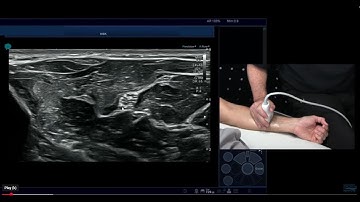

Peripheral nerve imaging with focus on inflammatory neuropathies